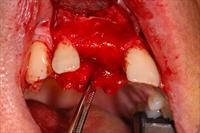

![]() 7. Four months post ridge split the site was uncovered in preparation for implant placement. |

![]() 8. The screw was removed, and a drill guidance system was used to place a 4mm wide platform Branemark implant. |